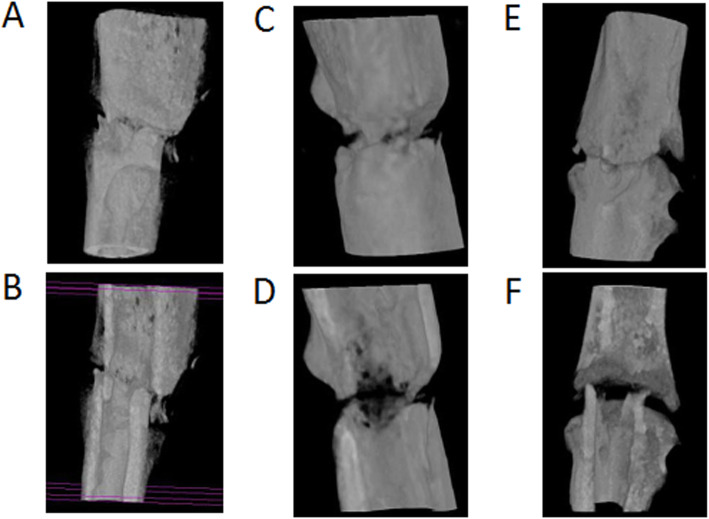

Histology

At 2 weeks after fracture, the control group model rats showed intramembranous ossification in the periosteal tissue and endochondral ossification at the fracture site (Fig. 6a). They formed a thick callus consisting of chondrocytes and newly formed trabecular bone, and the two calluses on each side of the fracture nearly united. The gap between the endochondral ossification areas was filled with mesenchymal cells. At the same time, the non-union group exhibited no chondrocytes or endochondral ossification on the site of periosteal cauterization (Fig. 6d). At 4 weeks after fracture, the callus at the fracture end of the control group had united (Fig. 6b). The bone of the fracture end was covered with newly formed trabecular bone and achieved bony union. In contrast, an obvious gap persisted between the surfaces of woven bone in the non-union group at 4 weeks (Fig. 6e). At 8 weeks, the united bone at the fracture end of the control group had remodeled (Fig. 6c). The fracture gap at the original cortical bone interface was bridged by newly formed woven bone, and the border between the cortical bone and newly formed woven bone could hardly be distinguished. In comparison, at 8 weeks in the non-union model, cortical bone resorption was seen at the fracture ends, and the cortical gap was more obvious than before (Fig. 6f). Some non-organized fibrous tissues were seen near the fracture gap. This is consistent with the histological finding of atrophic non-union.

Fig. 6.

Histological appearance with hematoxylin and eosin staining of the control group models (a–c) and non-union group models (d–f) at 2, 4, and 8 weeks. At 2 weeks after fracture, the control group models showed intramembranous ossification and endochondral ossification at the fracture site (a). However, there was no ossification on the site of periosteal cauterization in the non-union subjects (d). The fracture of the control group united at 4 weeks after surgery (b), while the non-union group models still had a large gap (e). At 8 weeks, the bridging callus in the control group had remodeled (c). In the non-union group, the gap was obvious, and the cortical bone began to be absorbed (f). Original magnification ×50